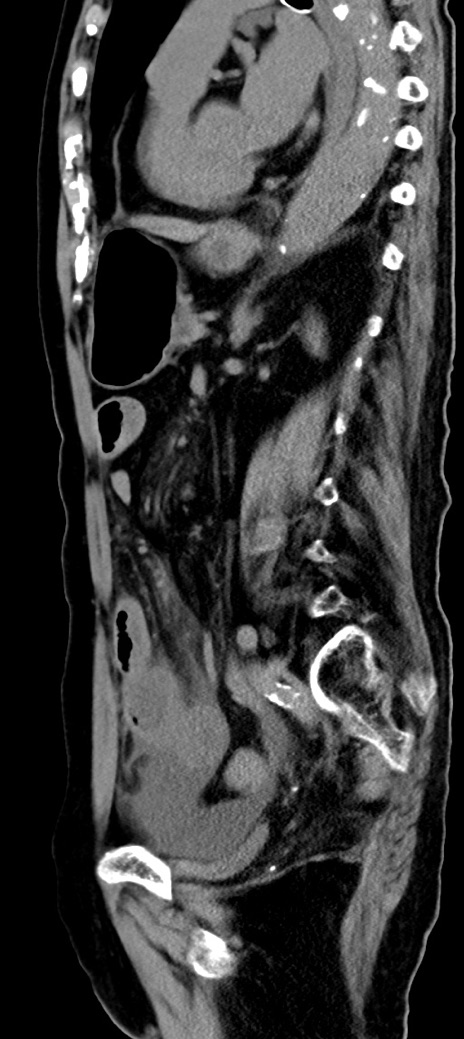

症例40(矢状断像)他院1日前

【症例】90歳代女性

【主訴】腹痛・嘔吐

【現病歴】 食欲低下、嘔吐があり昨日他院受診。肺炎と診断され入院となる。入院後より腹部全体に圧痛あり。胃管留置され経過みていたが、症状持続するため、

当院転院となる。

【既往歴】胸椎圧迫骨折、胆石症

【身体所見】腹部:中央に激痛あり、圧痛あり、反跳痛不明

【データ】WBC 17100、CRP 18.82